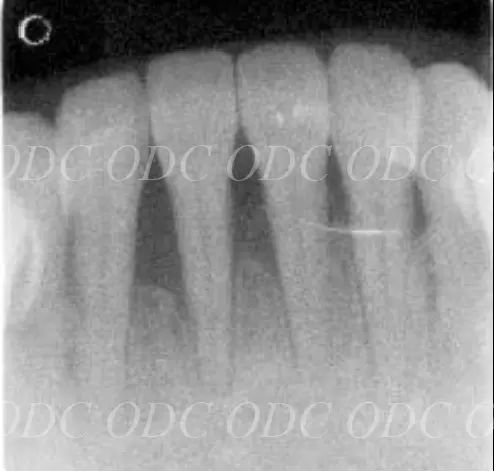

サイナスリスト症例

2008年、第一大臼歯の歯根破折を主訴に来院された。

サイナスリフト後にインプラント埋入。

左は術前のレントゲン写真。中央、右は2024年、術後約16年後のレントゲン写真と口腔内写真。

1枚目上、奥歯2本欠損でインプラント治療を希望された。サイナスリフト後、インプラント埋入。

2枚目、術後約10年経過。レントゲン的にも経過良好です。